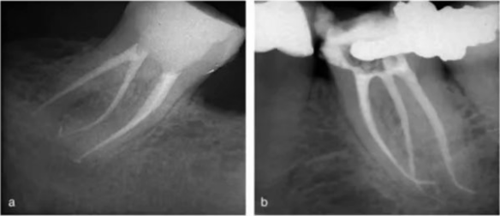

使用手術(shù)顯微鏡是非常有幫助的,特別是在那些根管口被鈣化物覆蓋的病例中,這些鈣化物可以使用超聲尖或長柄小球鉆輕松去除(圖 14a-d)。